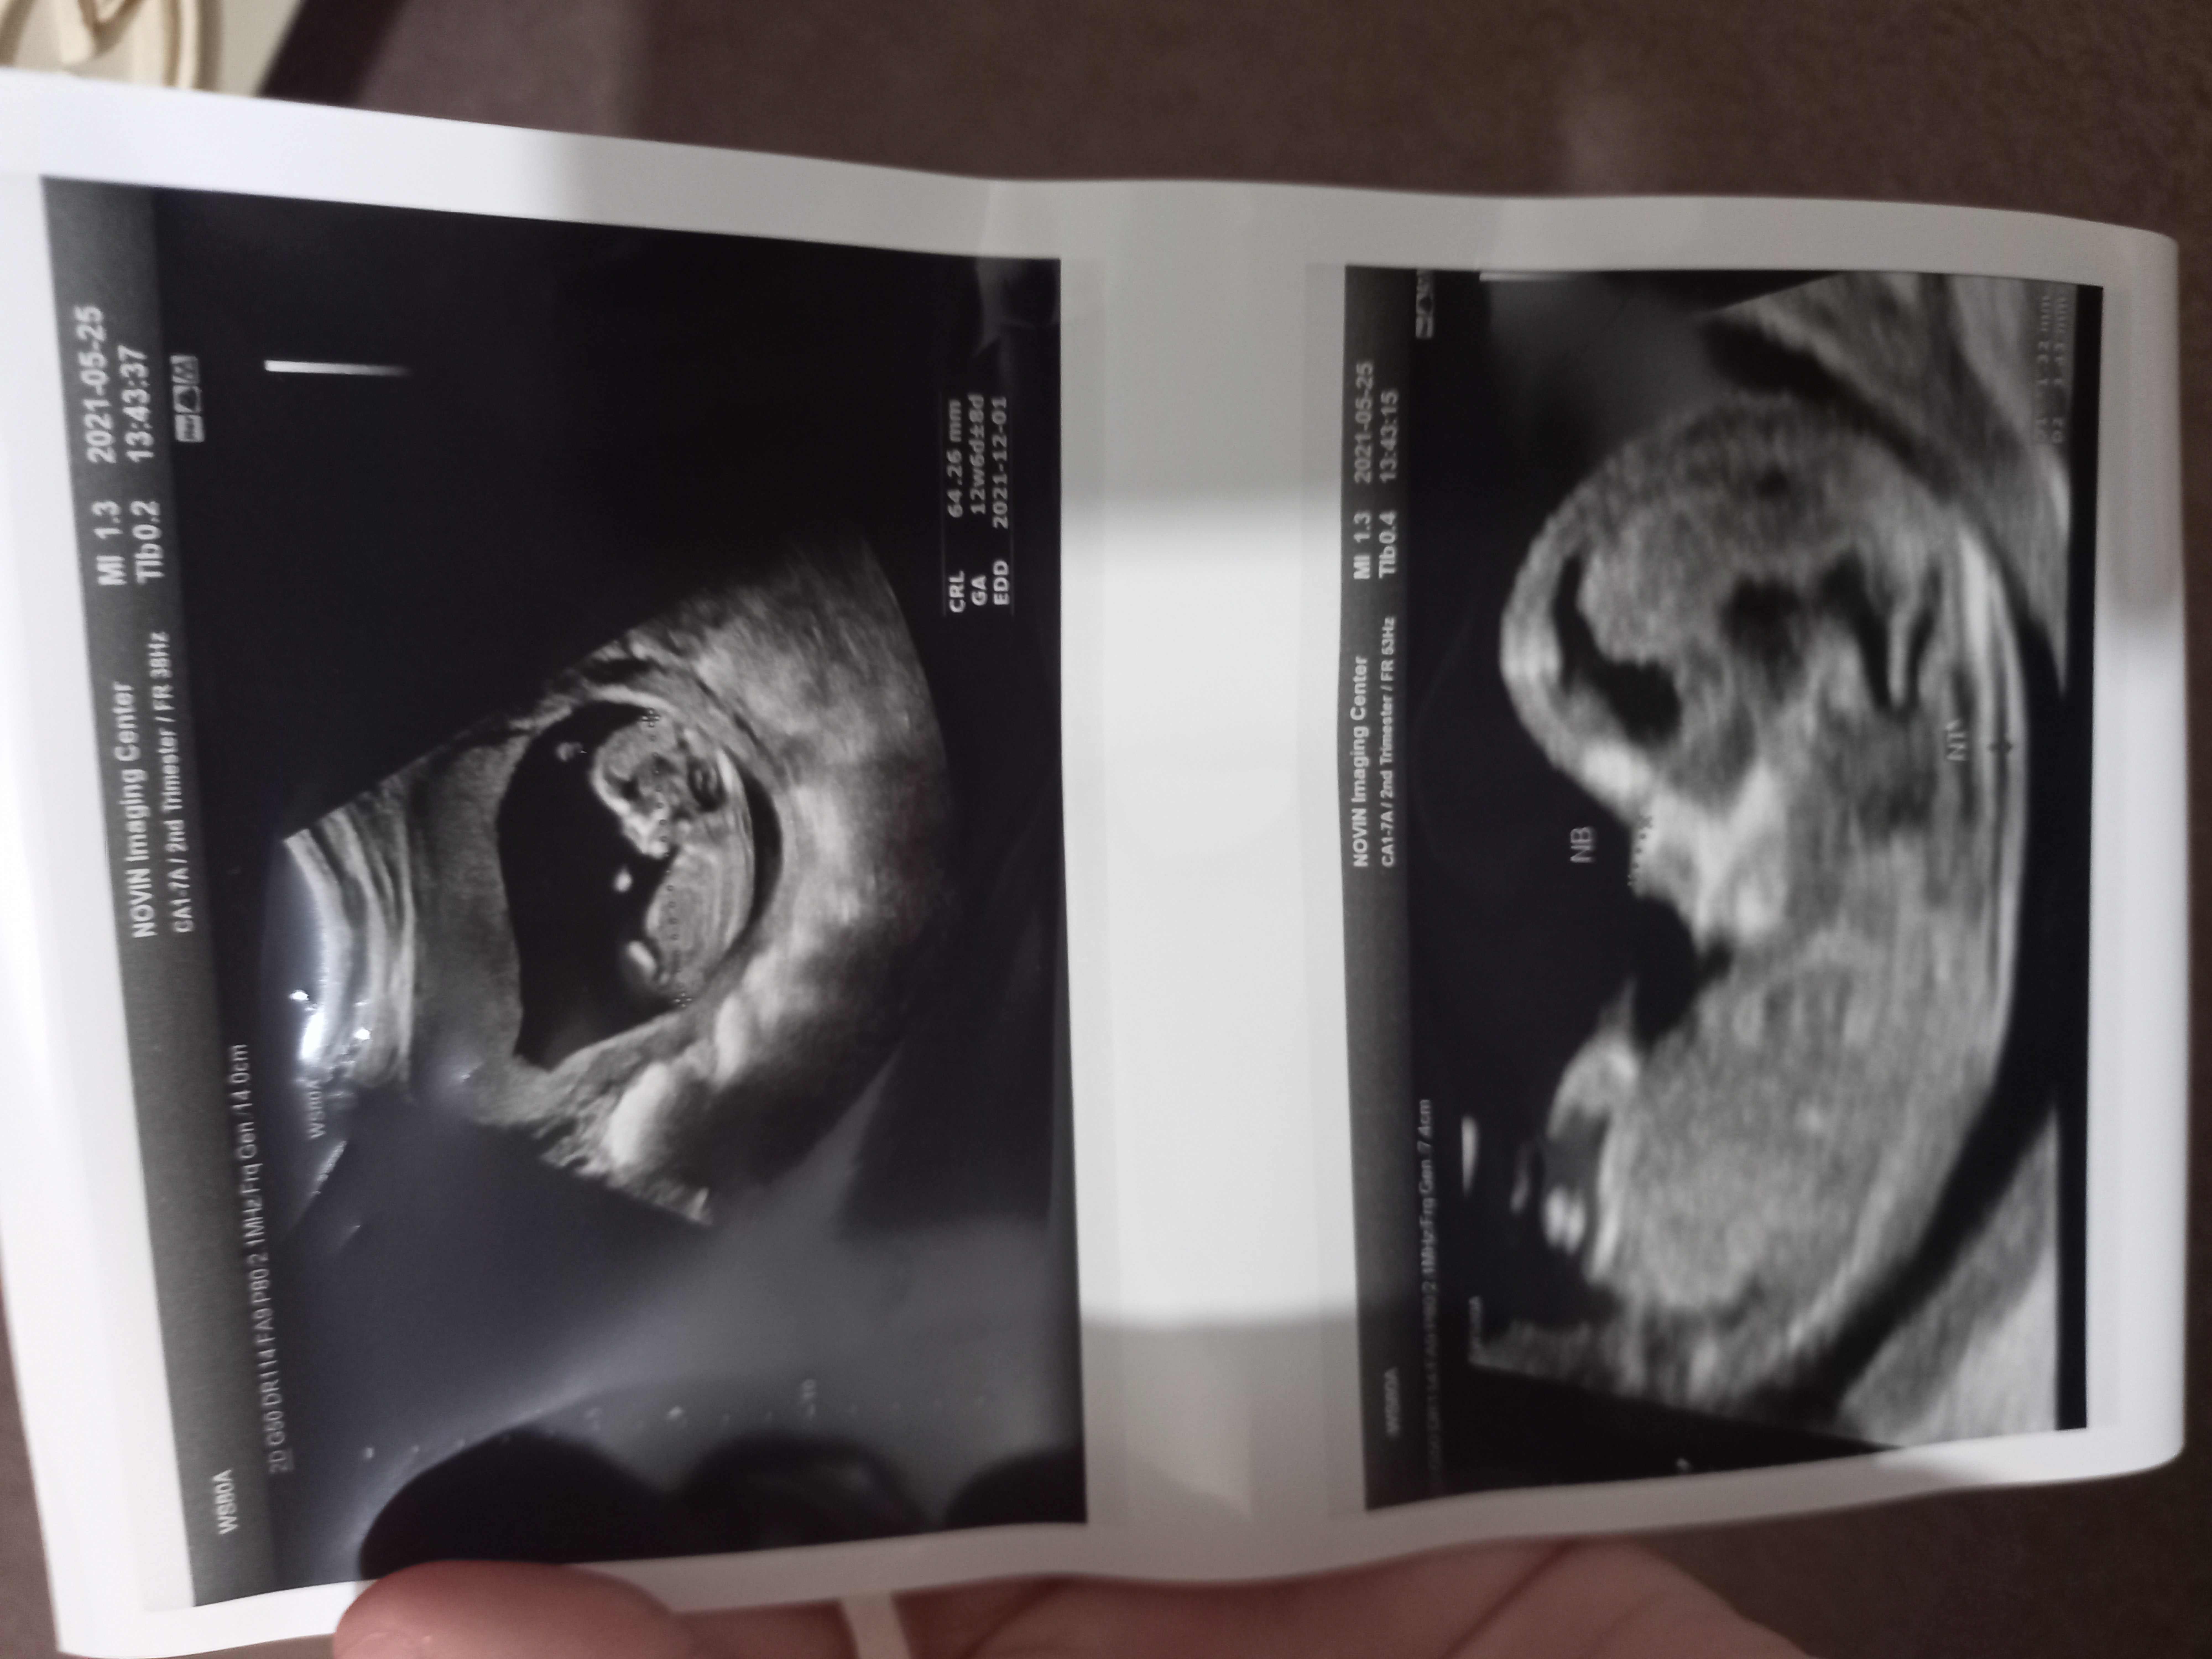

ida_f مدیر استارتر عضویت: 1398/10/18 تعداد پست: 1552 فقط همینه؟عکس دیگه ای داری؟؟؟شبیه پسره...اما مطمئن نیستم ...استخون مثانش یکمی نا واضح افتاده 🧿میخوام وحشی ، زیباوآزادباشم.. درست مثل دریا⭐🌊☃️

icegirl_h عضویت: 1398/12/09 تعداد پست: 2716 فقط همینه؟ اره هیمنه ب کوچیکترشم هس خیلی دوره فک نکنم بشه دید واصح اینه😐 ویهان کوچولوم نفس مامان🥺👶💙

ida_f مدیر استارتر عضویت: 1398/10/18 تعداد پست: 1552 شبیه پسره کاملاسلام و سلامت باشه همیشه ایشالله 🧿میخوام وحشی ، زیباوآزادباشم.. درست مثل دریا⭐🌊☃️